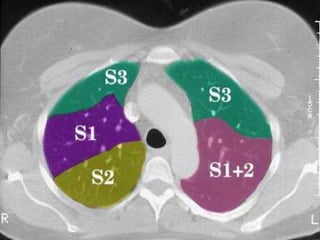

CAÂY PHEÁ QUAÛN VAØ PHAÂN

THUØY PHOÅI

+CT cho chi tieát giaûi phaãu toát raát nhieàu so

vôùi X quang qui öôùc

+Phaân tích hình aûnh CT

-Caây pheá quaûn

-Phaân thuøy phoåi

-Raõnh maøng phoåi

Ngang möùc

cung ñoäng

maïch chuû

3

2

1/21

6

Möùc Carina

1/2

Möùc ñoäng

maïch phoåi T

maïch phoåi P